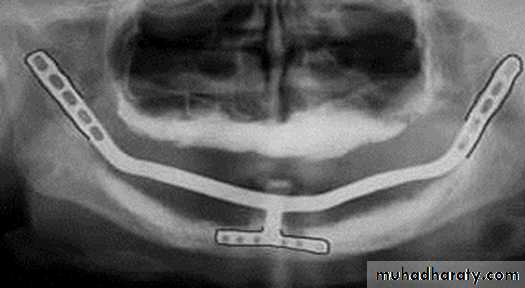

Transosteal / Transosseous Implant

Also called as Staple Bone Implant, Transmandibular ImplantPenetrates both cortical plate and passes through the entire thickness of the alveolar bone

Use restricted to anterior area of mandible

It is not used much any more because they necessitate an extraoral surgical approach.